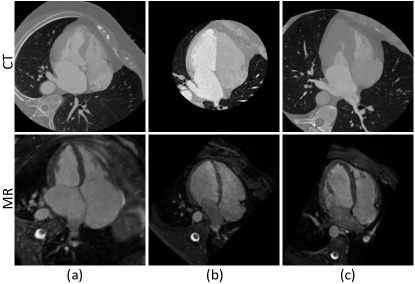

Figure 2: Cross-modality cardiac segmentation dataset. Images in the first and the second rows show some examples of two modalities, i.e. CT and MR. [Please indicate the data source]

Another widely used UDA application is for cross-modality data, and Fig. 2 provides examples of the cropped 2D images of CT and MR in cardiac segmentation. The data of different modalities has a larger domain-gap, which is more challenging. It is also worth noting that the cardiac cross-modality segmentation data have similar shapes, while retinal nonperfusion in the FA images has no fixed shape, and it is difficult to design a network structure that performs well on both cross-site and cross-modality applications.